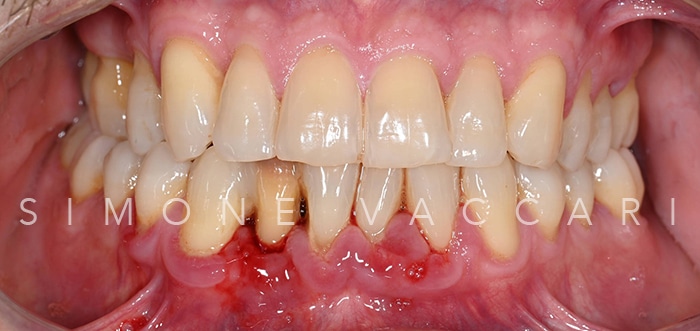

Michele bocca prima della cura della parodontite Prima

Michele bocca dopo la cura della parodontite Dopo